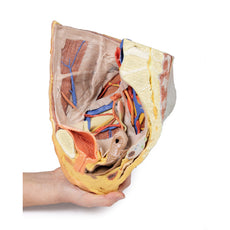

3D Printed Female Pelvis Deep Dissection

3D Printed Female Pelvis Deep Dissection

This 3D model presents a deep dissection and isolation of the pelvis from surrounding regions, particularly

demonstrating visceral and neurovascular structures relative to deep ligaments and osseous features.

Within the false pelvis, the sigmoid colon descends on the left side of the specimen to the rectum, passing

superficially across the pelvic brim and the passage of the common and external iliac artery and vein. Adjacent

to the sigmoid colon are parts of the sigmoid arteries and superior rectal artery, resting superficial to the

common iliac vessels and near the descending ureter. Anterior in the true pelvis is the collapsed urinary

bladder, and between the bladder and rectum rests the uterus. The organ is partially covered in the broad

ligament, with both the suspensory ligament of the ovary and round ligament have been separated and pulled away

from the peritoneum on both sides to expose surrounding blood vessels. While the ovarian ligaments, round

ligaments, uterine tubes and ovaries are trapped within the peritoneal fold of the broad ligament, the reduction

in ovary size (common with advanced age) has rendered these indistinguishable in the model.